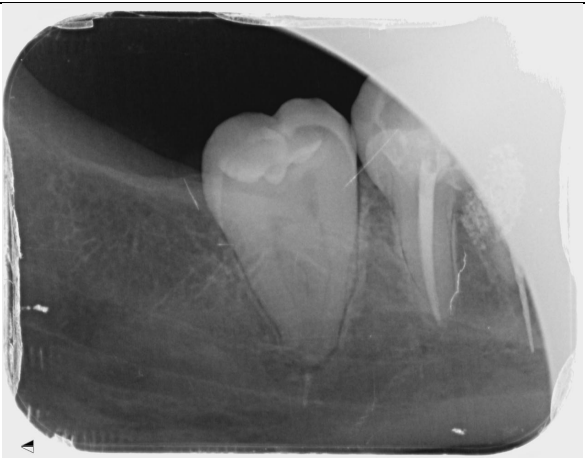

To assess the extent of the fracture and plan for removal, we obtained periapical radiographs and a cone-beam computed tomography (CBCT) scan. The imaging revealed the fractured NiTi instrument lodged deep within the canal system, complicating its retrieval due to its position approximately 8 mm beyond the apical foramen.

Fig 1, Fig 2, Fig 3, Fig 4, Fig 5, Fig 6, Fig 7

The patient was prescribed analgesics and instructed on postoperative care. A follow-up appointment was scheduled for one week later, during which she reported a significant reduction in paresthesia and overall discomfort. Radiographic evaluation confirmed the successful retrieval of the fractured instrument and the integrity of the root structure.

Figure 5

Figure 6